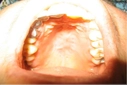

Hamilelikte takma diş damak yarası yaşadım ve gerçekten rahatsız ediciydi. Özellikle ağız hijyenine dikkat etmediğimde kanama ve hassasiyet arttı. Doktorum düzenli kontrollerin önemli olduğunu vurguladı. Umarım bu durumu yaşayan diğer hamileler de dikkatli olur ve zamanında önlem alır.

Geçmiş Olsun Kongurtay, yaşadığınız bu durumun ne kadar rahatsız edici olabileceğini anlıyorum. Hamilelik döneminde vücut birçok değişim geçiriyor ve ağız sağlığı da bunlardan biri. Ağız hijyenine dikkat etmek gerçekten çok önemli, çünkü bu tür yaralar hem rahatsızlık verebilir hem de daha ciddi sorunlara yol açabilir.

Düzenli Kontroller doktorunuzun da belirttiği gibi, düzenli kontroller hamilelik sürecinin sağlıklı geçmesi için kritik. Diğer hamilelerin de bu konuda bilinçlenmesi ve gereken önlemleri alması, hem kendi sağlıkları hem de bebekleri için oldukça önemli. Umarım, sizin gibi bu durumu yaşayanlar da bu süreçte daha dikkatli olurlar. Sağlıklı bir hamilelik dönemi geçirmenizi dilerim.